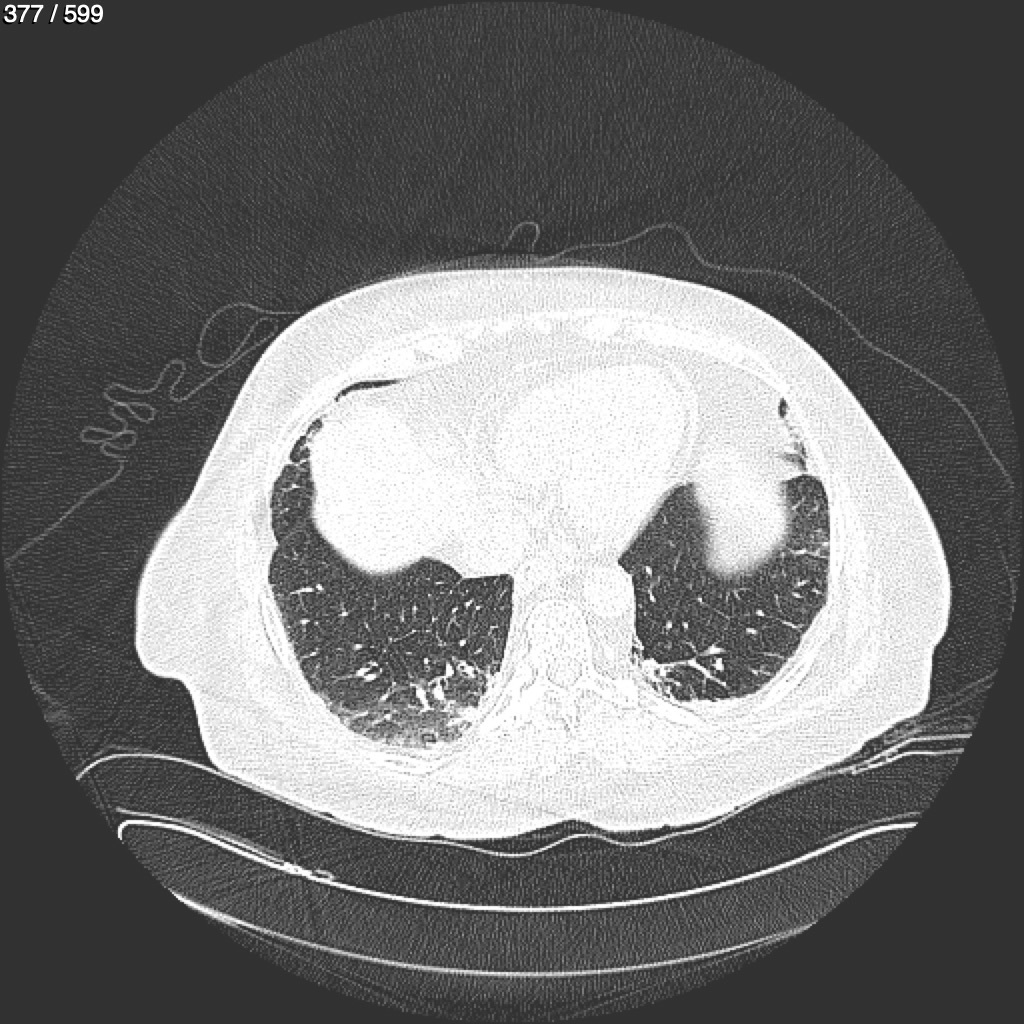

Home G​l​o​r​i​a​ ​G​l​a​d​y​s​ ​B​e​a​s​l​e​y​ ​-​ ​T​ó​r​a​x​ ​T​o​r​a​x​_​S​i​m​p​l​e​ ​(​A​d​u​l​t​o​)